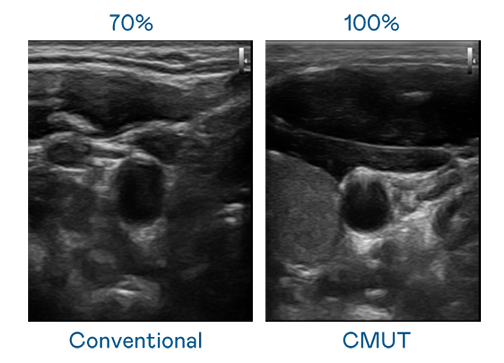

CMUT 技术是一种用电容式微机电元件来产生超音波讯号的技术。与传统 PZT 压电式技术相比,CMUT 频宽增加 30%,更宽频的超音波讯号让影像解析度大幅提升,是实现高影像品质医疗超音波扫描、促进精准医疗发展的关键技术。

超音波影像的解析度高低,首先取决于探头能发出的讯号频宽。AB娱乐 CMUT 可提供高清晰的超音波讯号,提供高频宽、高灵敏度、影像纹理细节更高的超音波影像,协助医护人员缩短影像判读时间及利用精准的医疗影像进行诊断。